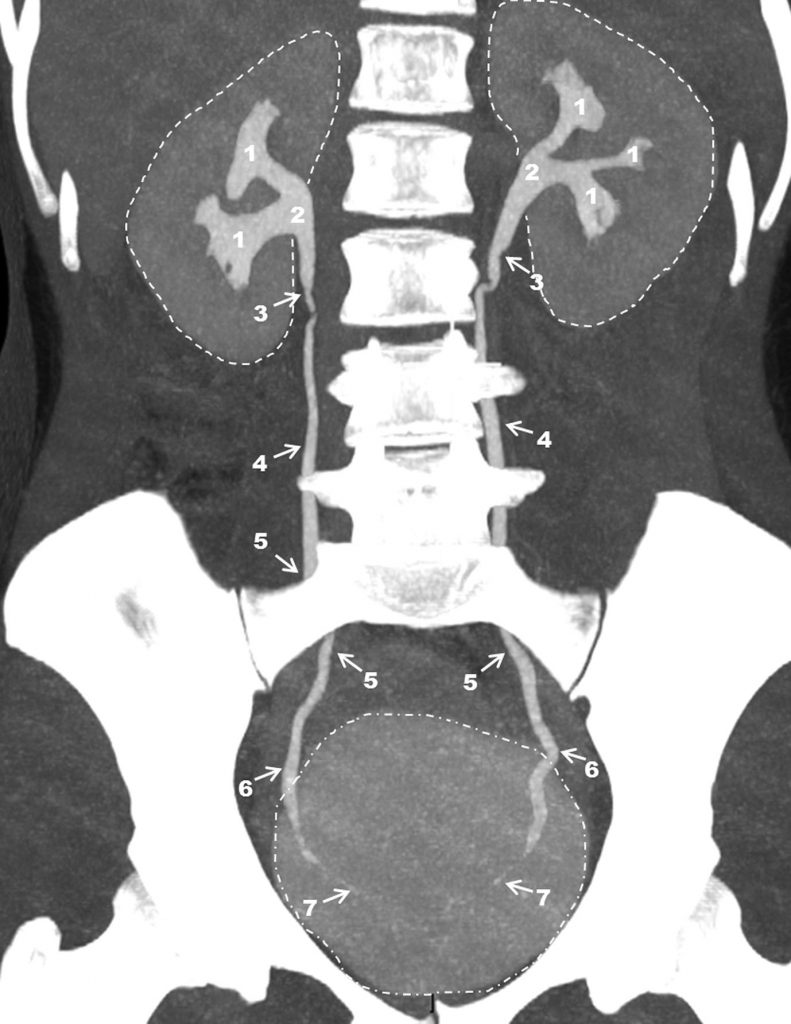

Fig. 19.5. Uroscanner : reconstruction en mode MIP (Maximal Intensity Projection) 10 minutes après injection intraveineuse du produit de contraste iodé.

Reins et vessie pleine opacifiée (lignes pointillées). 1, 2. Appareils collecteurs. 1. Grands calices. 2. Pelvis rénal. 3. Jonctions pyélo-urétérales. 4. Uretères lombaires. 5. Uretères sacro-iliaques. 6. Uretères pelviens. 7. Segment préméatique intramural des uretères.

Source : CERF, CNEBMN, 2022.